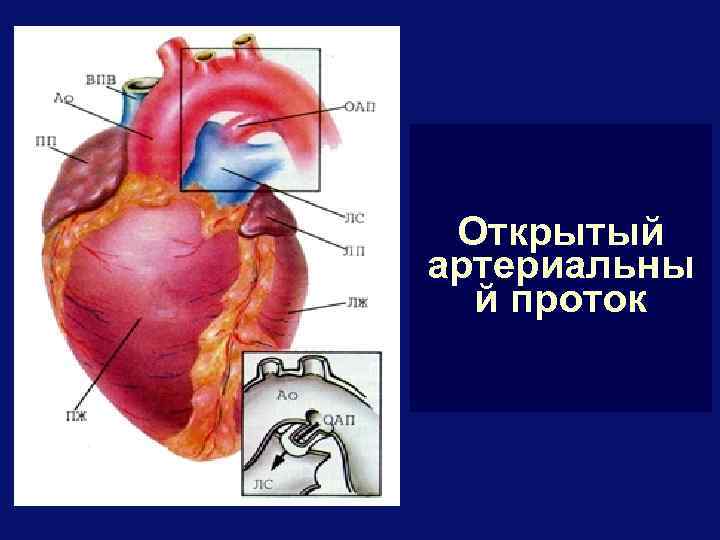

Открытый артериальны й проток

ОАП - лечение § Если ОАП функционирует более 6 мес. – абсолютное показание к операции, поскольку развитие легочной гипертензии у большинства больных неизбежно § Оптимальный возраст 2 -6 лет § Виды вмешательств: § открытая резекция и перевязка протока § торакоскопическое клипирование и пересечение протока § РЭ- окклюзия протока § Летальность – 0 -3%

Перевязка ОАП